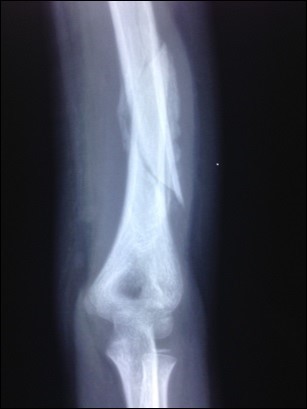

Table 1 below serve to summarize the characteristics of the patient population and the mean time for fracture union. Figure 1 and Figure 2 showed serial radiological appearance of one of the patients with upper limb delayed fracture consolidation of mid-shaft of the humerus despite casting for 5 weeks in a public hospital. Figure 2 was taken after LLLT administration showing not only obvious solid bony healing, but also very good re-modelling.

Figure 1.Partially united and angulated humerus shaft fracture prior to LLLT administration in one patient